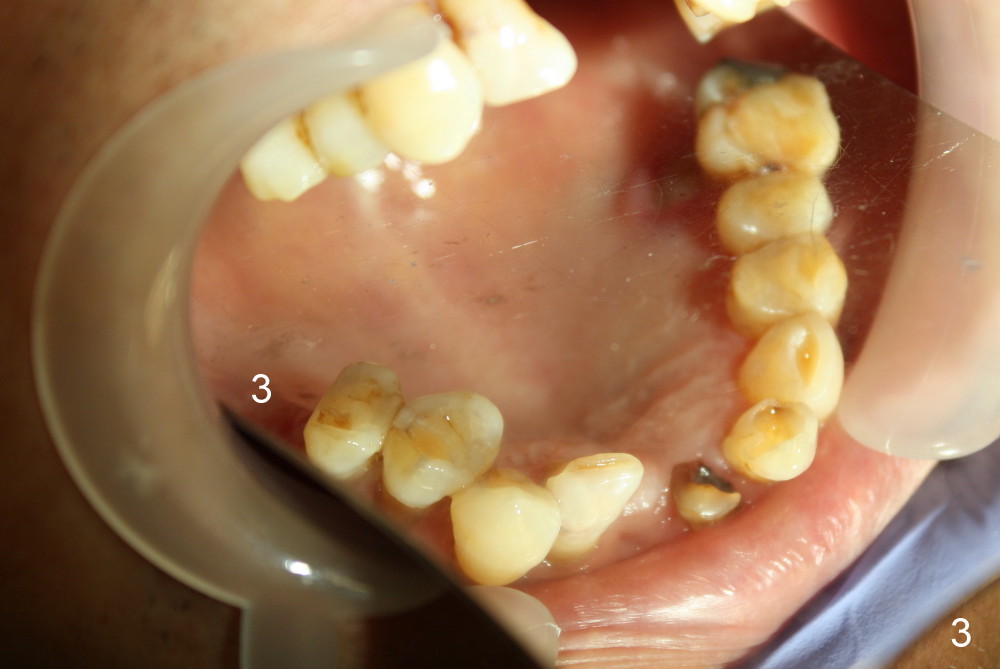

First molar occlusion is planned (1,2). The tooth #3 was extracted a year ago (Fig.1 (CT sagittal section). There is more bone loss distally so that bone graft (red circles) is required post implantation (5.3x14 mm). Buccolingual width is not severely compromised (Fig.2 (coronal section), 3).

Buccal atrophy at the site of #8 dictates a smaller implant than that of #9 (Fig.4-7).